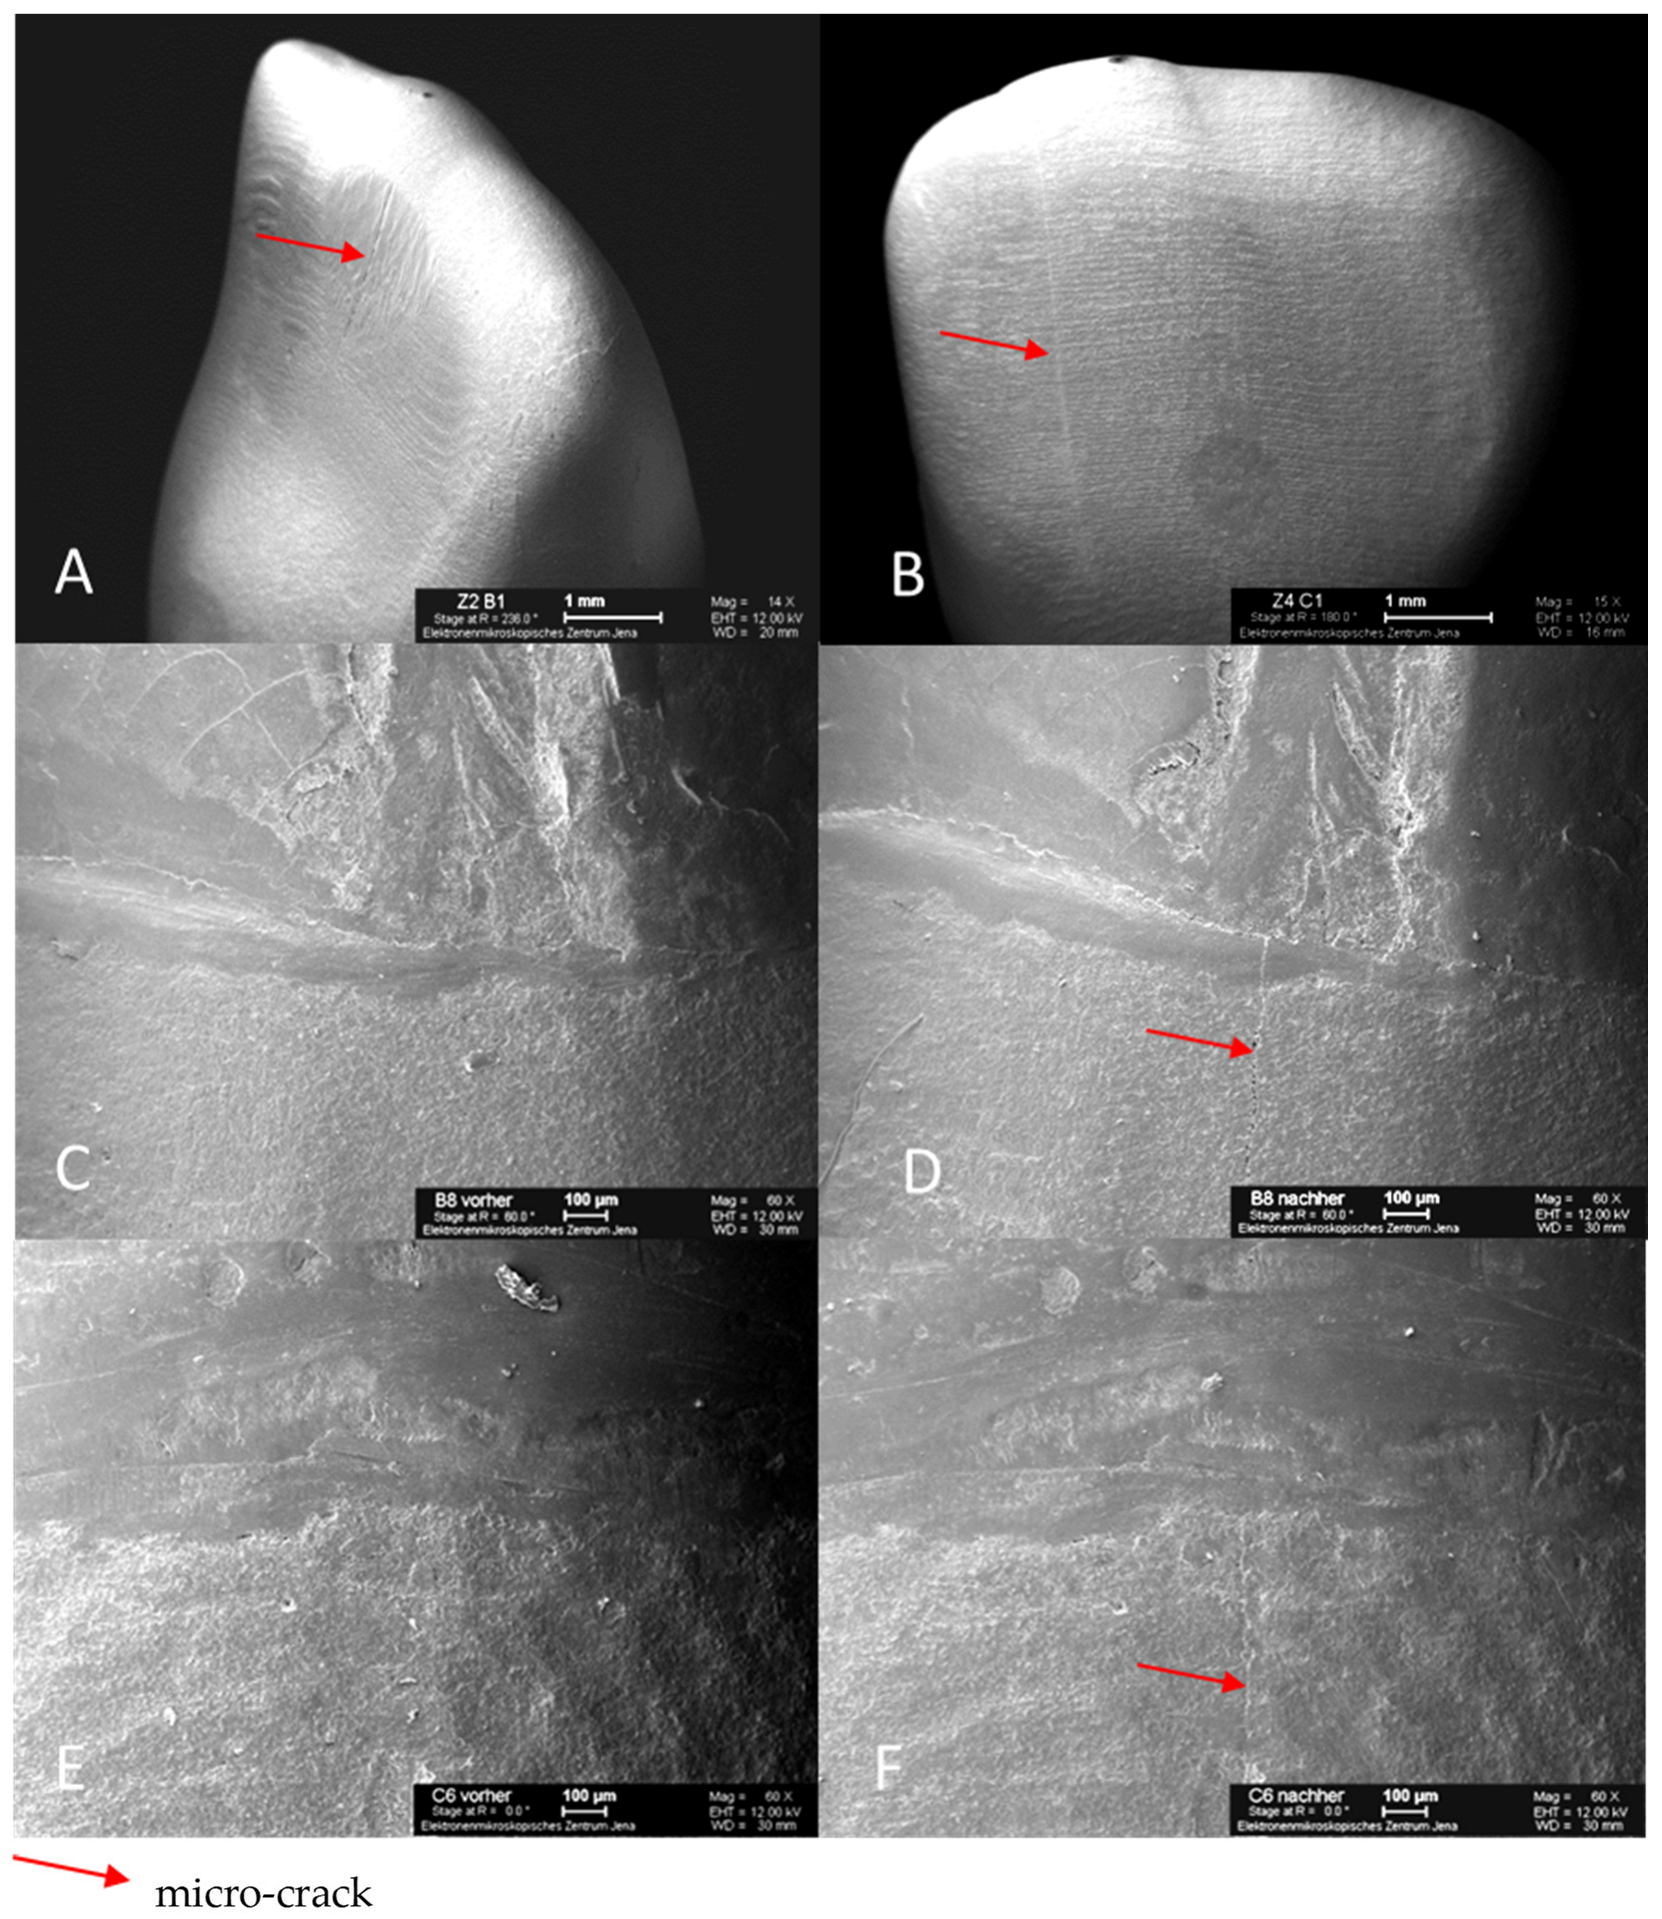

Representative scanning images of all-ceramic crowns with micro-cracks illustrate the dimension and the variable courses of the micro-cracks, which are marked with arrows. The same areas of the marginal gap are shown both before and after TCML. The root surface is at the top, and the all-ceramic crown is at the bottom of the SEM image (Figure 8). After TCML, fine micro-cracks can be seen in the area of the ceramic. In addition, neither widening of the marginal gap nor structural loosening is evident.

Figure 8.

SEM images of specimen tooth B1 (glass-fiber L9) after TCML with micro-crack on the palatal surface of the crown (A); specimen tooth C1 (glass-fiber L6) after TCML with micro-crack on the labial surface of crown (B); specimen tooth B8 (glass-fiber L9) before TCML, marginal gap (C); specimen tooth B8 (glass-fiber L9) after TCML, with micro-crack in marginal gap area (D); specimen tooth C6 (glass-fiber L6) before TCML, marginal gap (E); specimen tooth C6 (glass-fiber L6) after TCML, with micro-crack in marginal gap area (F).